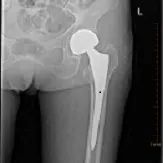

1、股骨頸骨折

術(shù)前

人工股骨頭置換術(shù)后